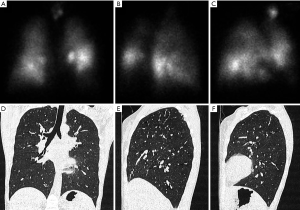

Scintigraphy

A different imaging modality, which can be used in the evaluation of severe lung emphysema is scintigraphy (Figure 3). With scintigraphy it is possible to visualize ventilation and perfusion of the lungs. With this method upper-lobe predominance and heterogeneity of emphysematous lung changes can be visualized and combined with functional data such as perfusion. The technique is especially helpful in the evaluation for the detection of severely emphysema affected areas in the lung in heterogeneous emphysema, but struggles in subjects with a homogeneous distribution of emphysema (36). In scintigraphy the lung is divided in three distinct zones (i.e., upper, middle and lower zonr). Information on tracer uptake, corresponding to ventilation and perfusion, are provided for these three distinct lung zones.

Some authors, despite the high agreement between lung perfusion evaluated on HRCT and on scintigraphy, criticize scintigraphy for the lack of additional information to HRCT making scintigraphy superfluous in the assessment of lung emphysema (37,38).